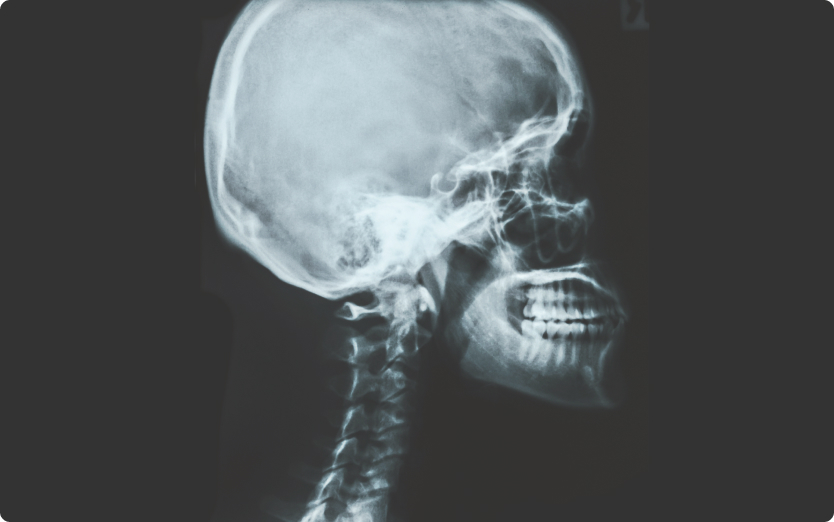

- ・噛み合わせと脳血流量には関係性があるという研究結果もあります。